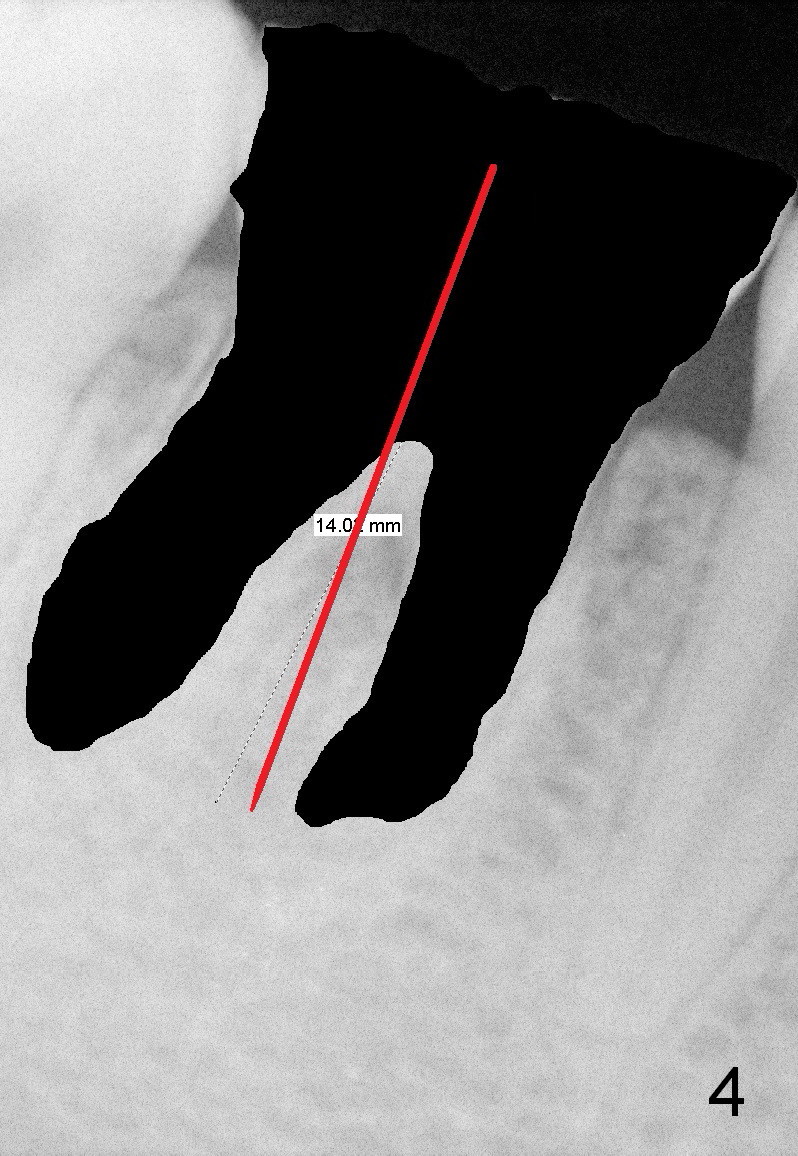

First of all, use a sharp small pilot drill (1.2, 1.5 or 2.0 mm) 3 mm shy of the extended length.  For this case, the initial depth will be 14 mm from the gingival margin (Fig.3: red long arrow).  If the drill is straight and in the middle of the septum (1st intraop PA), keep drilling for the next 3 mm.  If the trajectory is off (Fig.4), withdraw the drill (Fig.5 black long arrow), find a new starting point, change the trajectory and finish osteotomy depth (red long arrow) if the new trajectory is deemed correct.  Take more X-ray if necessary.